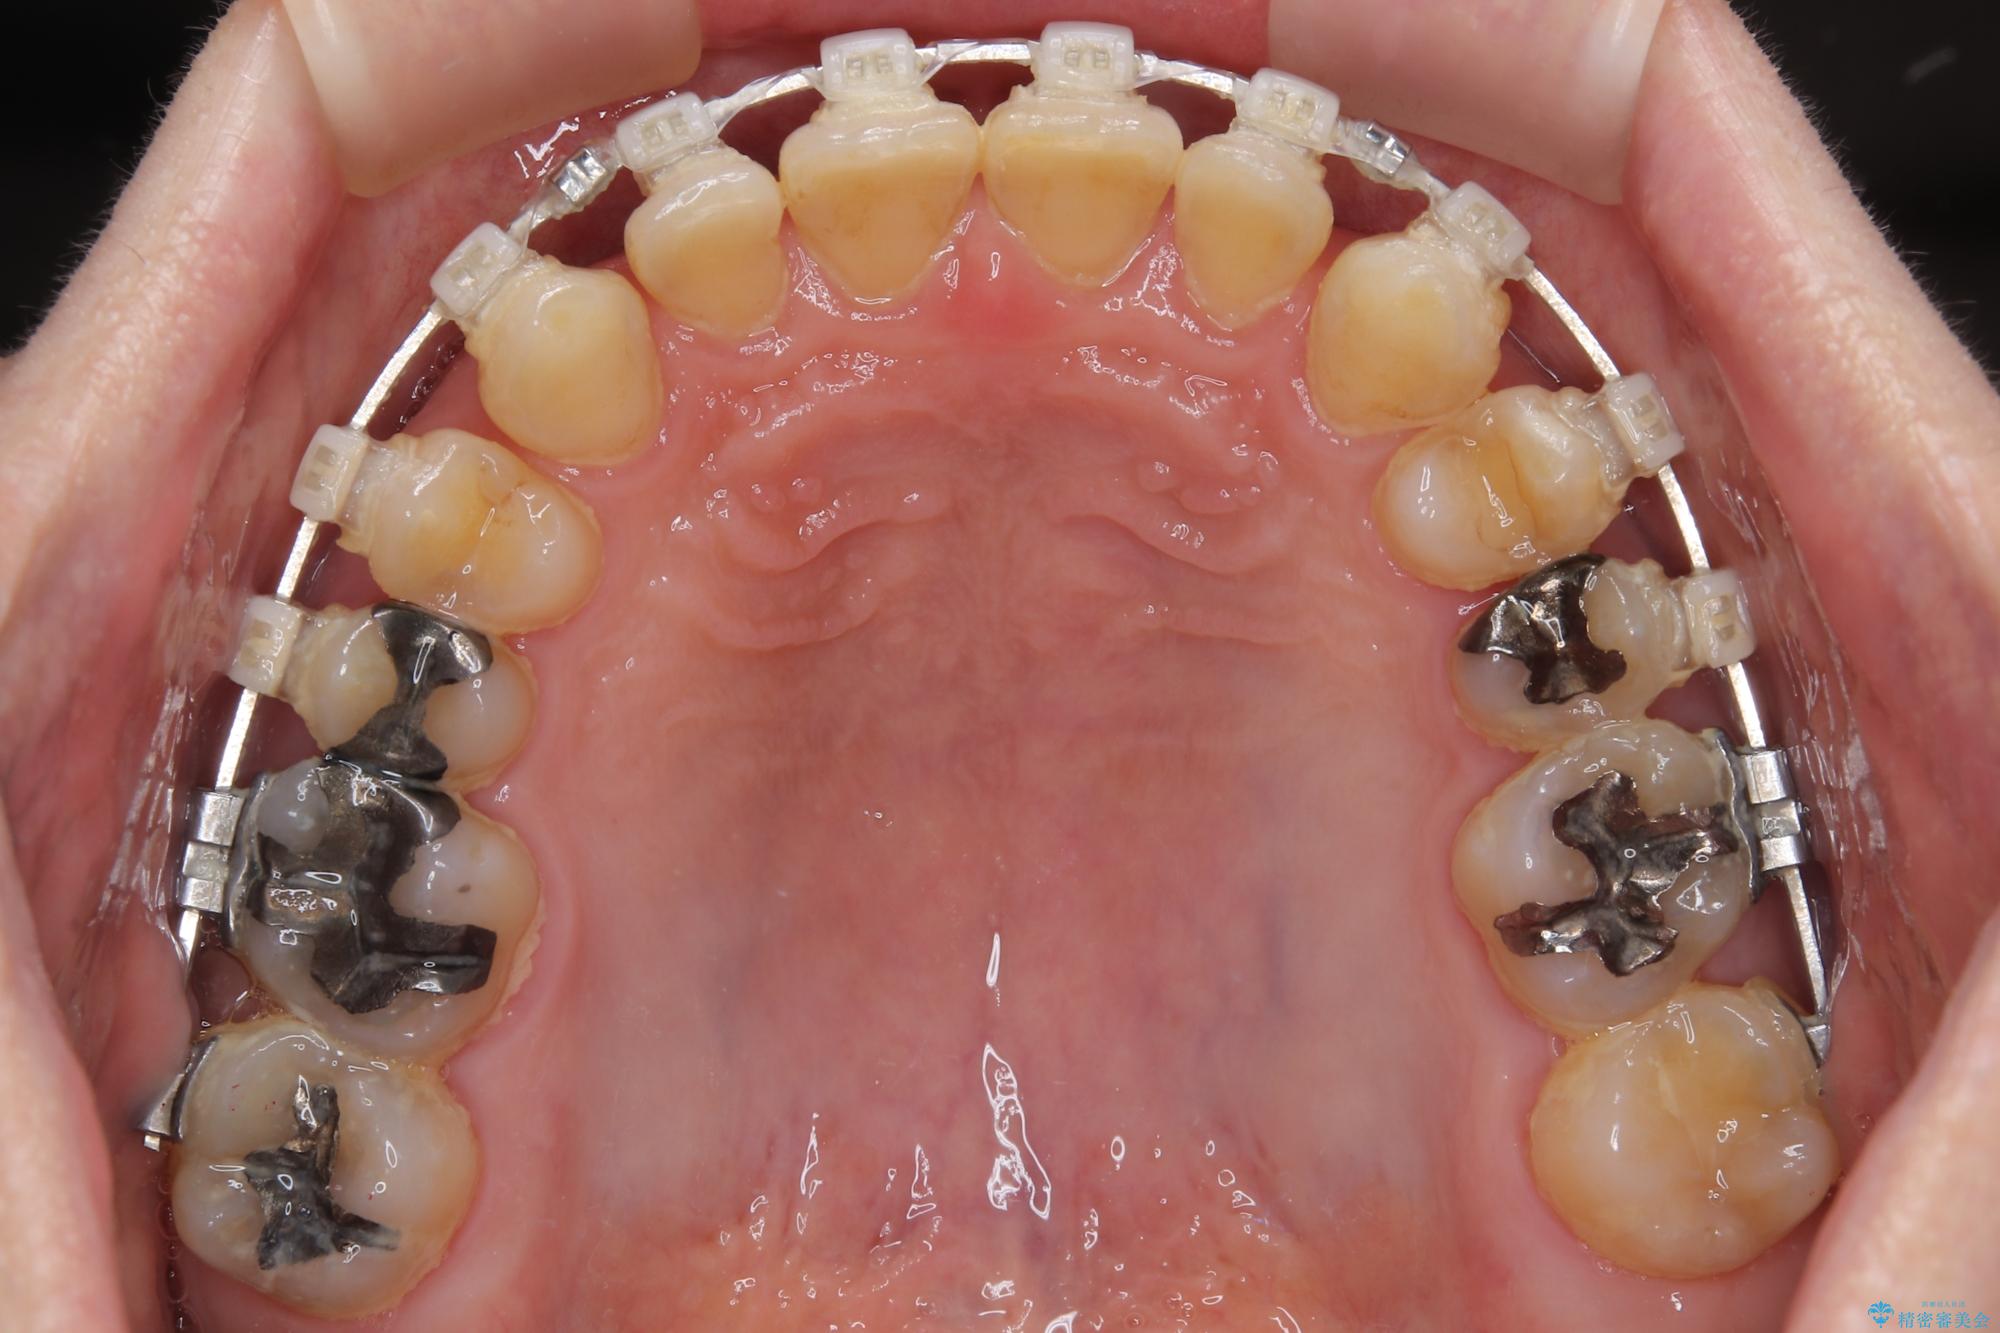

【モニター】ディープバイトで隙間の空いた歯列 ワイヤー装置での非抜歯矯正

- 前歯のデコボコと隙間の空いた歯列を気にして来院された患者様です。

下顎前歯が隠れるほどのディープバイトにより、強い咬合力と突き上げで上顎歯列に隙間が空いている状態でした。

手前に傾斜している奥歯をワイヤー装置で立ち上がらせ、咬み合わせの高さを挙上することで突き上げを解消し、空隙歯列を改善していくこととしました。